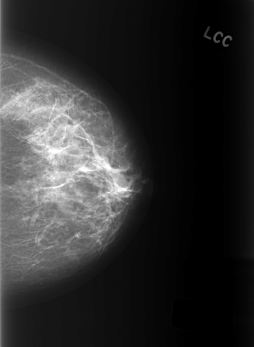

C_0402_1.LEFT_CC

LEFT_CC LINES 5552 PIXELS_PER_LINE 4056 BITS_PER_PIXEL 12 RESOLUTION 50 NON_OVERLAY